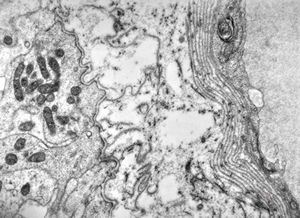

M,1y. | plexus papilloma